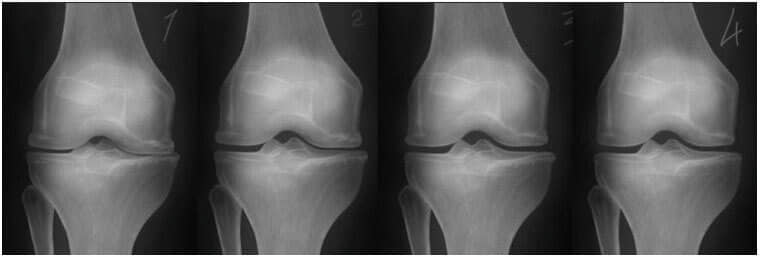

Onda se dogodilo čudo. Ovaj doktor je počeo svaki dan dolaziti kod Nermine i mazao je ovom ljekovitom mašću. Nekoliko sedmica kasnije, uspjela je da ustane iz kolica i da sama ode kod doktora. Nakon šest sedmica, zglobovi Nermine Arnautović su se potpuno oporavili od osteoartritisa. Snimci su to pokazali.

S lijeve strane: Snimak zgloba koljena Nermine

Arnautović, 75. Hrskavično tkivo je potpuno uništeno. Preporuka

doktora je da se uradi operacija koljena i da se zglob zamjeni

vještačkim.

S desne strane: Snimak zgloba

desnog koljena Nermine Arnautović nakon liječenja gelom Nautubone.

- Snimak ispod pokazuje tipičnu sliku oporavka zgloba koljena.